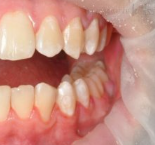

Профессиональная гигиена особенно важна при ортодонтическом лечении, ведь в повседневной жизни, дома, очень сложно поддерживать должный уровень гигиены полости рта! Даже если вы используете ирригатор и специальные ёршики! В нашей рубрике «до/после» вы видите то, что может быть с зубами при лечении брекетами, если не проводить своевременную чистку у врача-стоматолога. Марухно Дарья Александровна провела профессиональную чистку в несколько этапов, чтобы вернуть пациентке белизну ее собственных зубов! Брекет-система была поставлена не в нашей клинике, и почему пациентка не обратилась за профессиональной помощью раньше-вопрос) Но в данном случае, главное – итог! Кровоточивость после даже обычной чистки в такой клинической ситуации – естественный результат. Ведь обильный зубной налёт и зубной камень вызывают воспаление дёсен в виде гингивита, а порой даже пародонтита.

Доктор: Марухно Дарья Александровна